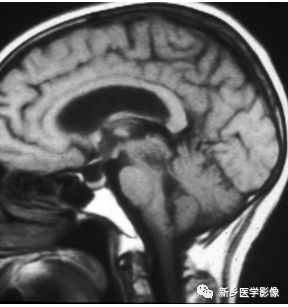

松果体囊肿

松果体囊肿常见,MRI的发现率约为5%,尸检发现率约为20%-40%。其通常小(80%小于1cm),大部分无症状,尤其是小病灶。当病灶较大时,可表现为占位效应,压迫中脑顶盖导致上丘脑受压及出现帕里诺综合征【注:又称上丘脑综合征,中脑顶盖综合征,上仰视性麻痹综合征。由上丘脑病变(多为松果体肿瘤压迫中脑四叠体)而导致的眼球垂直同向运动障碍,向上凝视麻痹、瞳孔对光反射消失(上丘受损);神经性聋(下丘受损);小脑性共济失调(结合臂受损)。症状多为双侧。】

矢状位及横断位T1WI示松果体区囊性肿块。病灶内信号相对于脑脊液稍高,可能由其内蛋白成分所致,横断位T2WI及FLAIR呈高信号,T1WI+C示无强化,邻近强化静脉血管可见。